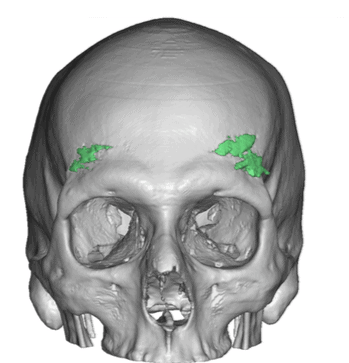

Desire for head shape asymmetry improvement as the final stage of total skull reshaping surgeries. (previous skull implants are in green color)

Placement of custom temporal implant through an incision behind the ear.

Desire for head shape asymmetry improvement as the final stage of total skull reshaping surgeries. (previous skull implants are in green color)

Placement of custom temporal implant through an incision behind the ear.